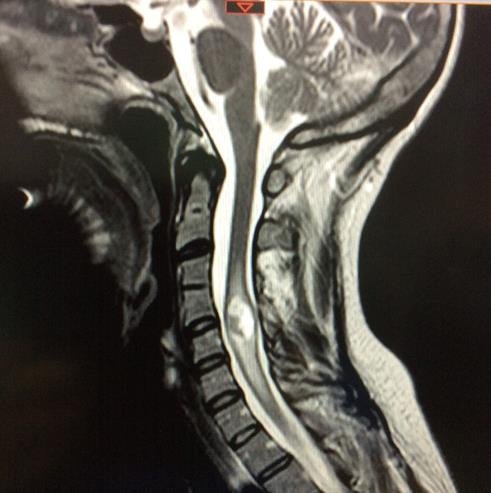

Prueba de elección para tumores de columna y médula espinal. Evalúa partes blandas, relación con la médula y raíces, y detecta compresión, edema, necrosis o hemorragia intratumoral.